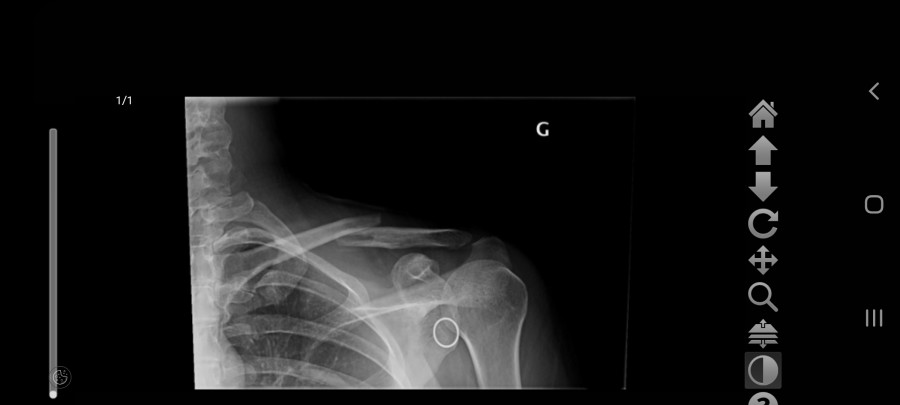

vicky2011 Oui c'est ça, ils n'opèrent que rarement car trop de risques de léser nerveusement voir d'hémorragies importantes (et effectivement 6 ans après je n'ai pas encore retrouvé la même qualité de sensation au niveau de la peau environnante et ai régulièrement des fourmillements très très agaçants vu que c'est un peu une démangeaison fantôme ), ils essaient autant que possible de réparer mécaniquement avec un cal osseux, mais dans mon cas ils ont quand même sérieusement merdé vu que dès le début il était assez flagrant que ça ne pouvait pas revenir en place mécaniquement

Stricto sensu de mémoire j'avais le "droit" de remonter dès les traits de fracture enfin comblés, mais tout en étant avertie qu'une nouvelle grosse chute pouvait faire de considérables dégâts vu que ça ne pêterais pas au niveau de l'osteosynthese mais a côté ... honnêtement j'ai tellement dégusté durant ces quelques mois et surtout avec la greffe osseuse qui s'en est suivie pour combler le bout d'os nécrosé ( du fait des mois d'attente )que je n'avais aucune envie de tenter le diable , je suis remontée au bout de quelques mois mais très occasionnellement, et refroidie , avec gilet airbag (puis projet bébé, puis elevage, donc ça a clairement marqué un tournant dans ma vie equestre , autant je n'avais pas d'appréhension de chuter avant autant désormais ce n'est plus le cas, pourtant sur le coup ça allait, c'est vraiment les mois de galère et douleur qui m'ont un peu "traumatisé"je pense ); je n'ai osé remonter sans airbag qu'une fois les broches retirées